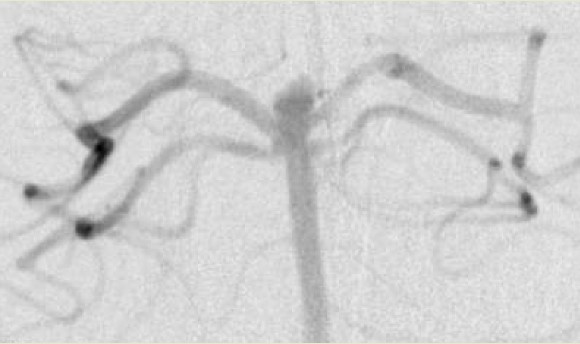

椎动脉造影(放大图像)示一个微导管(*)从左侧ICA通过左侧PCoA,经动脉瘤颈进入左侧PCA,并终止于右侧PCA远端。第二个微导管(@)位于动脉瘤中。

椎动脉造影(放大图像)示弹簧圈位于动脉瘤内,支架横跨瘤颈支撑弹簧圈。